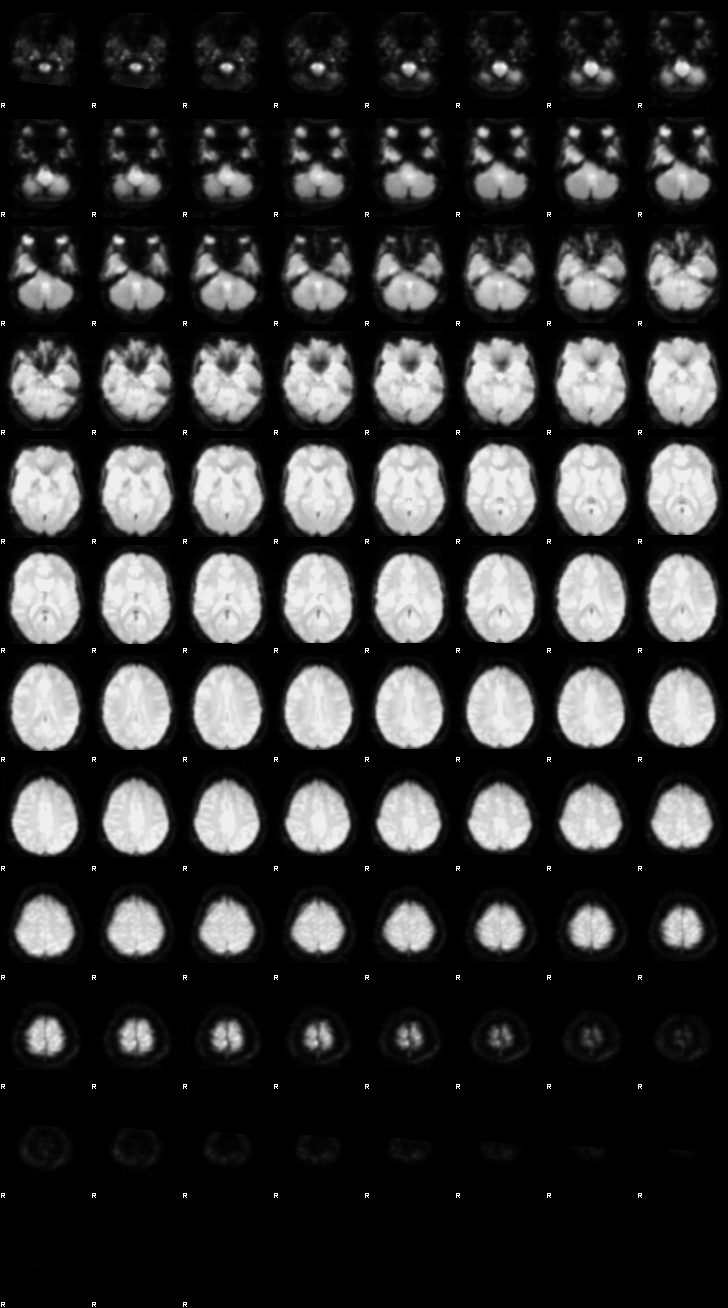

Let’s now display the thresholded activation maps. A voxelwise threshold of Z > 3.1 was applied, followed by cluster-level correction at p < 0.05 (corrected for multiple comparisons).

zstat1 - C1 (incongruent)

zstat2 - C2 (congruent)

zstat3 - C3 (incongruent-congruent)

display(Markdown("#### Incongruent"), rendered_thresh_zstats1)

Incongruent

display(Markdown("#### Congruent"), rendered_thresh_zstats2)

Congruent

display(Markdown("#### Incongruent-Congruent"), rendered_thresh_zstats3)

Incongruent-Congruent